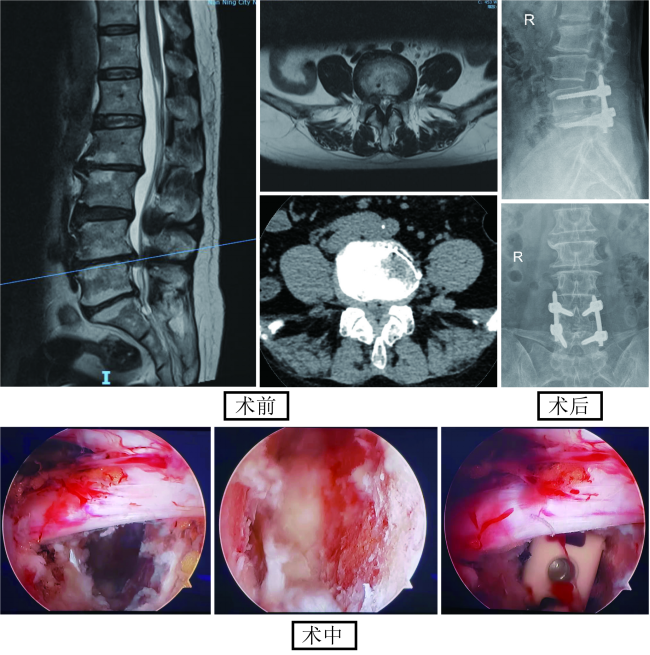

3.脊柱微创内镜技术治疗腰椎间盘突出症

(1)在椎间孔镜下,于椎间盘纤维环外手术,彻底清除突出或脱垂的髓核和增生的骨质来解除对神经根的压迫,消除由于对神经压迫造成的疼痛,使用椎间孔髓核切除术可以精确的对椎间盘进行手术而不触及健康组织。因此可以最大程度地保持纤维环的完整性和保持脊柱的稳定性,在同类手术中对病人创伤最小、效果最好。局麻下操作,术后当天即可下地活动。

图注:术前MRI提示腰4/5/椎间盘脱出向上游离,使用侧路椎间孔镜穿刺定位,术中可见白色髓核突出,术中直视下切除突出髓核组织。

(2)EndoP/TLIF开展小切口微创髓核摘除纤维环修复术、保留椎板的椎管潜行减压术,手术创伤小、恢复快,术后第二天可下床活动。

图注:开展微创小切口髓核摘除纤维环修复术,创伤小,特别合适年轻腰椎间盘突出症患者

(3)UBE开展小切口微创髓核摘除纤维环修复术、保留椎板的椎管潜行减压术,手术创伤小、恢复快,术后第二天天可下床活动。